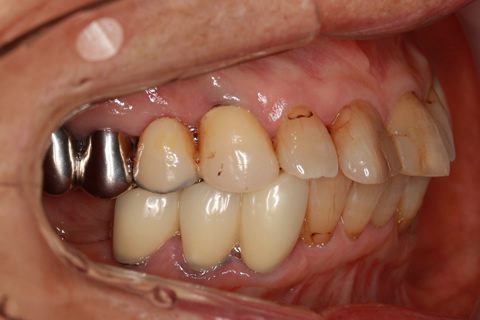

• 症例2

治療前

インプラント埋入時

治療後

年齢・性別

57歳男性

治療期間

3ヶ月

抜歯

なし

治療費

154万円

備考

左上5.6.7 及び左下6.7欠損

治療内容

左上5.6.7と左下6.7欠損部にインプラント埋入

施術の副作用(リスク)

オペによる知覚障害。インプラントによる歯肉炎。インプラント脱落。